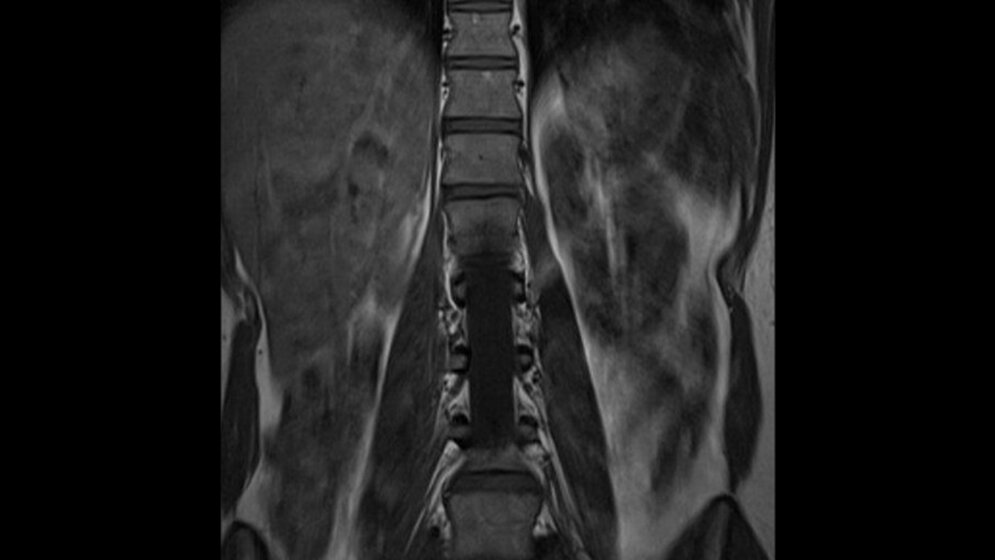

Zufallsbefunde: Nierenagenesie

Schnittbilddiagnostik der Wirbelsäule (7.20)

Die aktuelle Publikation zeigt eine Nierenagenesie rechts als weiteren Zufallsbefund.